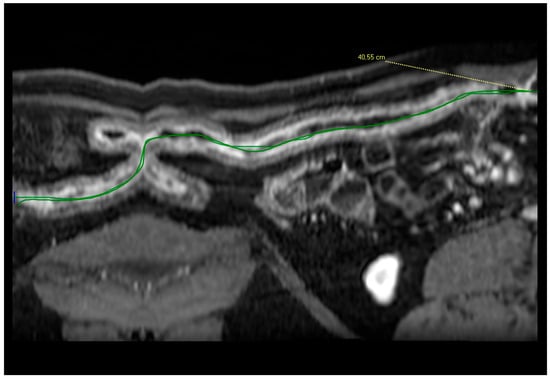

- Minordi, L.M.; Larosa, L.; Brizi, M.G.; Armuzi, A.; Manfredi, R. Length of the healthy and pathological small intestine in patients with Crohn’s disease: Calculations using computed tomography and magnetic resonance enterography. Diagn. Interv. Radiol. 2023, 29, 24–28. [Google Scholar] [CrossRef]